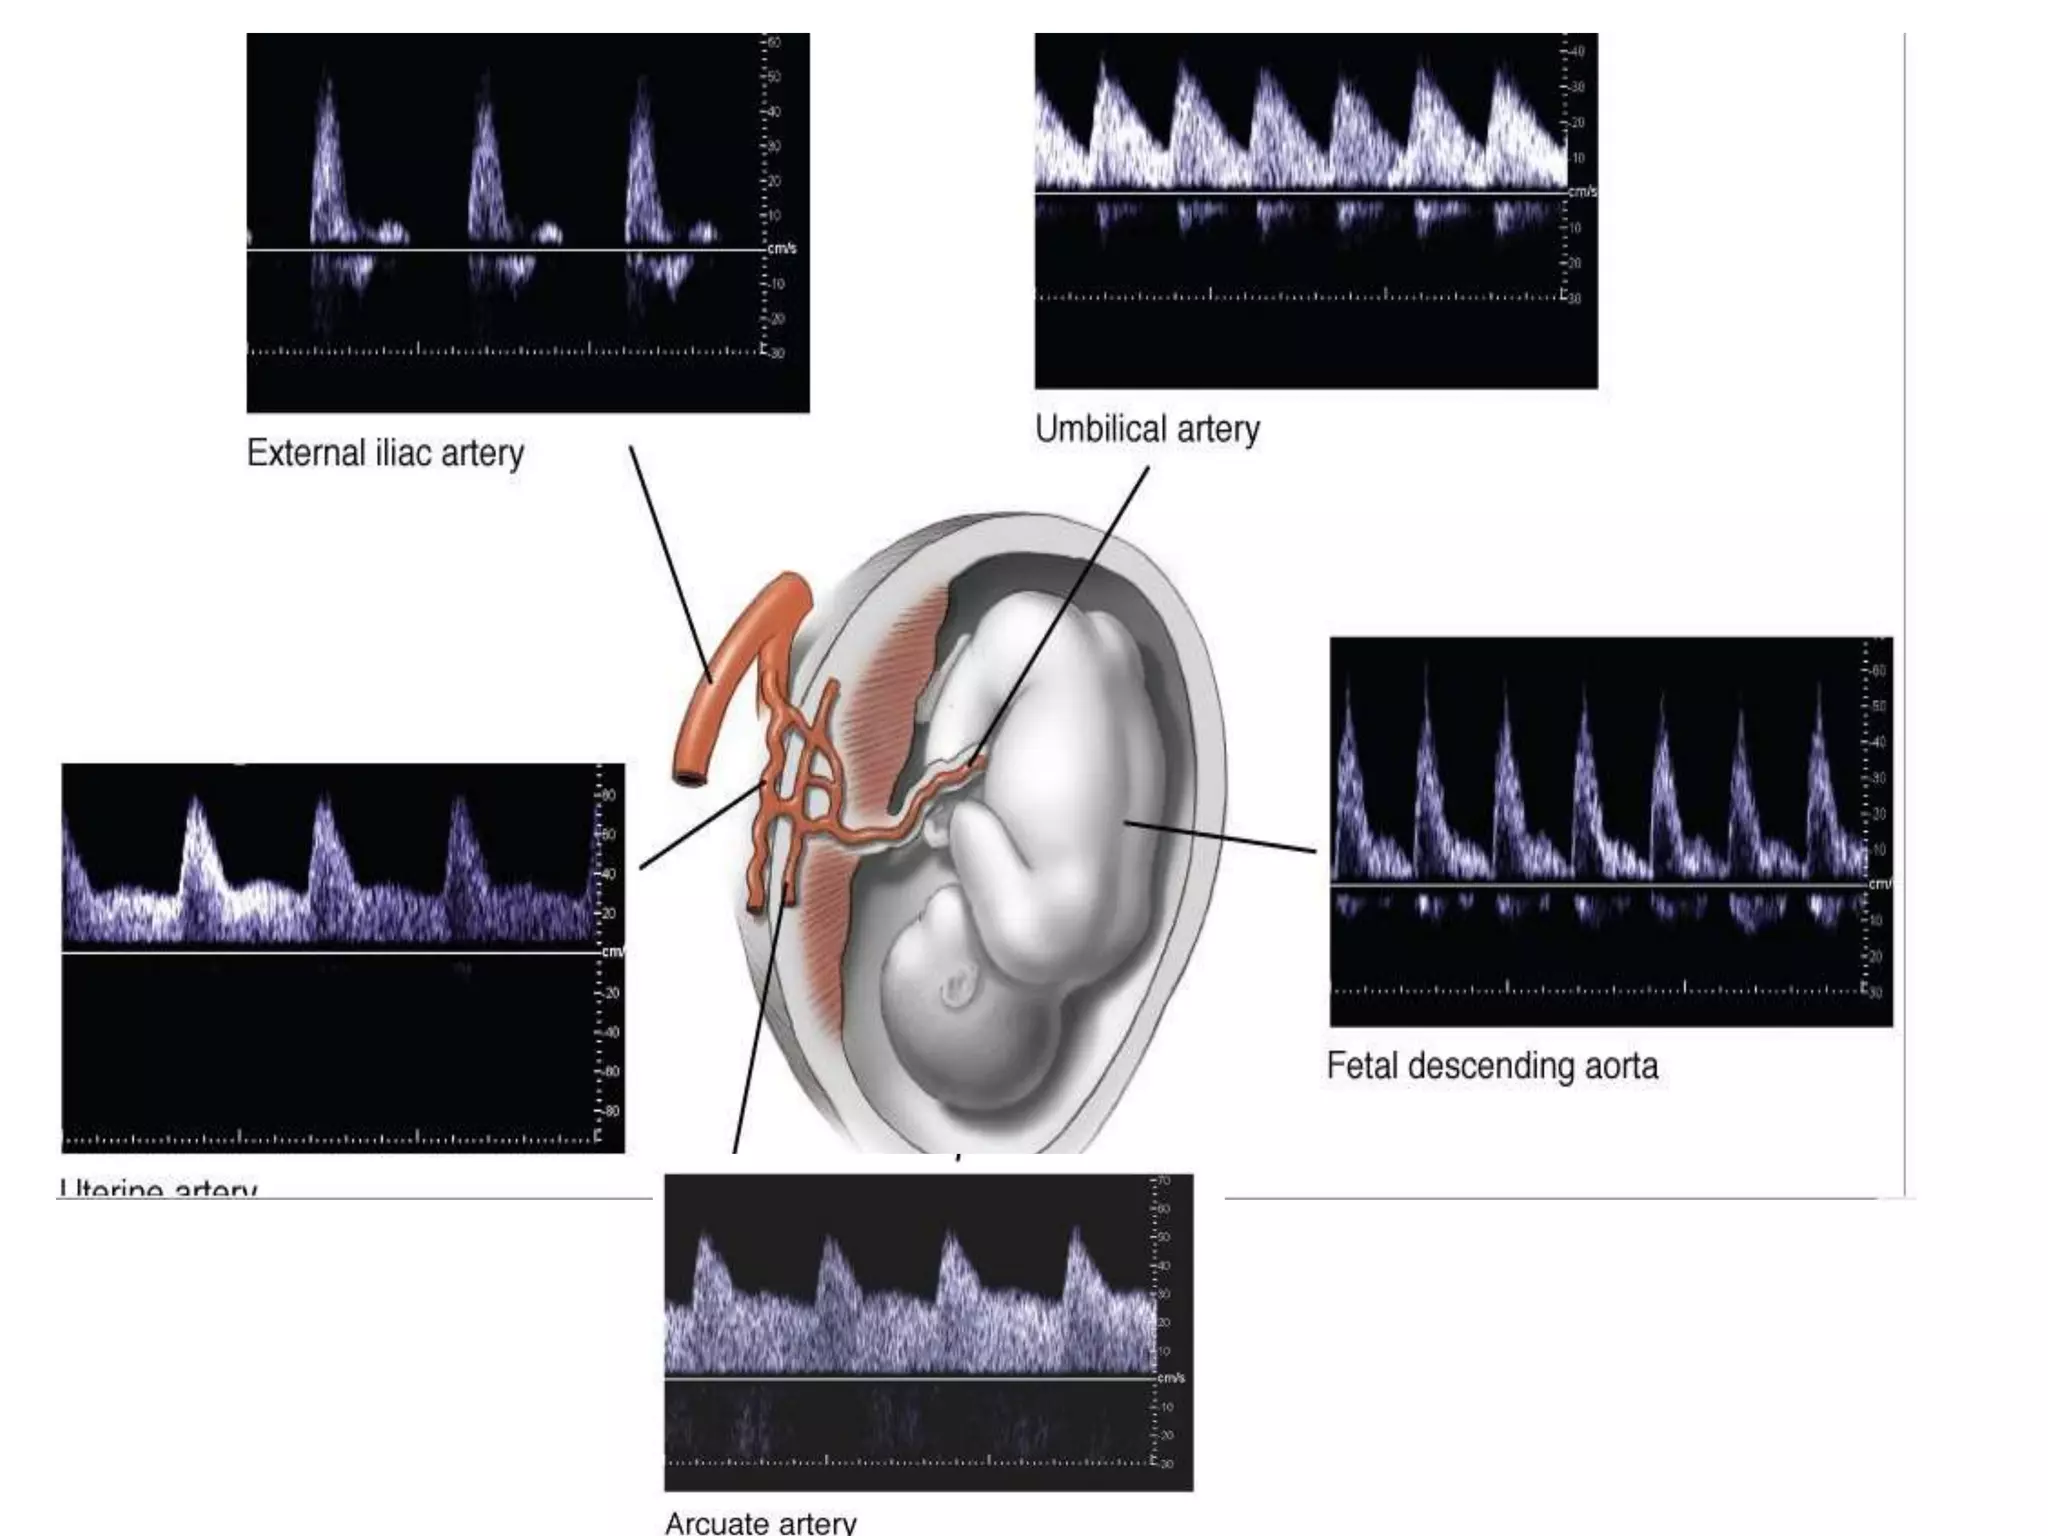

Technique of color Doppler

• Pt is 1st screened in the routine fashion using B mode using

3.5 or 5 MHz curved array transducer.

• The vessel of interest is located by color doppler.

• The spectral doppler wave form is then obtained by placing

the doppler gate directly over the vessel of interest.

• These recordings should be done in the absence of fetal

breathing movement and fetal heart between 120-160.No

fetal movements

• The best wave form is obtained when angle of insonation is

between 30-60 degree. Difficulty is faced when fetus is

moving or vessels are not linear i.e. umbilical artery.

• The pulse repetition frequency and wall filter is kept minimum

in order to not obscure minimal end diastolic flow when

present.

(1)Changes in the arterial circulation 

(a) Uterine circulation----as the feto- placental

compartment develops and gestational age advances ,

there is an increase in number of tertiary stem villi and

arterial channels to meet the need of developing fetus.

hence the Doppler study at this time shows

appearance of a diastolic component in uterine artery

flow velocity wave form,. during early 2nd trimester

i.e.. 14 weeks’ gestation and progressively increases

Up to 24 weeks.                        in normal

pregnancy it continued to show increased diastolic

flow velocity and loss of diastolic notches by 22weeks .

• (b)Umbilical Artery-It is direct reflection of

placental flow. umbilical artery is assessed at

three sites--- the placental origin ,fetal

abdominal insertion site and in the middle of

free floating vessel.

Resistance at abdominal insertion site

is higher and progressively decreases towards

placental site.(figure 5)

In normal fetus ,pulsatile index (PI)

decreases with advancing gestational period.This

indicates progressive decrease in vascular

resistance in placental bed.(figure 6)

• (d) Fetal Aorta It reflects the cardiac out put and the

peripheral resistance of systemic circulation, it gives

the summation of blood flow information to kidneys,

abdominal organs lower limbs and placenta.

• Normal blood flow in fetal descending aorta is highly

pulsatile with minimal diastolic component.

• Diastolic velocities start to present in 2nd and 3rd

trimester. Pi remains constant(1.7-1.8)